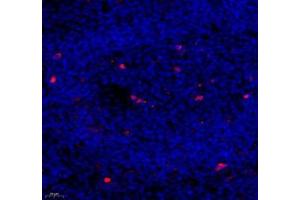

Caspase 3 抗体

(Caspase 3 (CASP3))